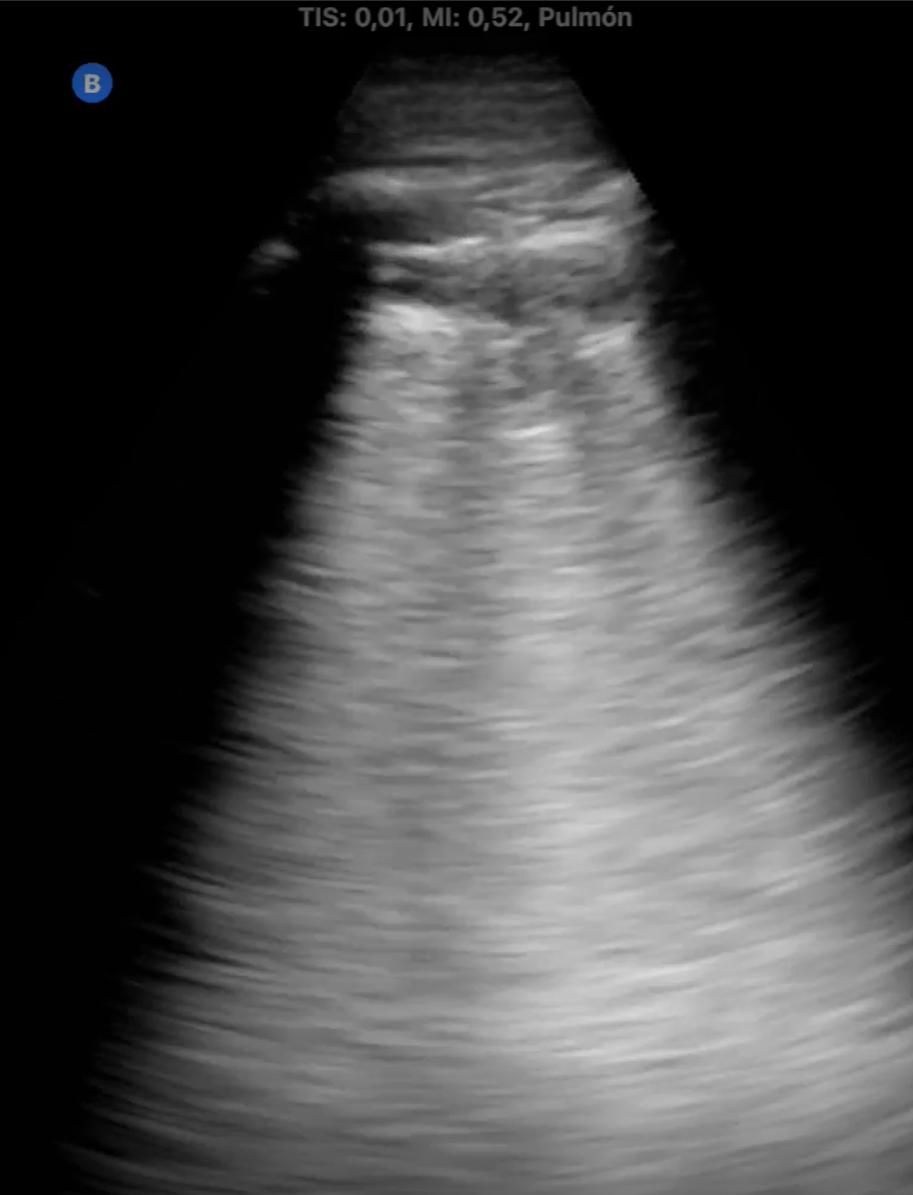

La medicina de familia no tiene horarios ni fronteras. Durante el último año, hemos incorporado el ecógrafo ultraportátil a nuestra vida diaria no como un recurso improvisado, sino como una herramienta integrada en nuestra práctica diaria capaz de dar respuesta inmediata a demandas clínicas surgidas en el entorno comunitario. En este contexto, han surgido situaciones en las que la ecografía ha sido determinante: diagnóstico de neumonías en domicilio, confirmación de roturas fibrilares tras actividad deportiva, fractura costal, valoración de hematomas y complicaciones postquirúrgicas, e incluso la identificación de una enfermedad pulmonar intersticial. Todo ello fuera del centro de salud, sin acceso a historia clínica ni a pruebas complementarias, únicamente con la sonda, la experiencia clínica… y una gran responsabilidad emocional. Estas situaciones generan un desafío distinto: no hay anonimato, y la confianza.

La ecografía ultraportátil amplía la capacidad resolutiva del médico de familia más allá de la consulta. Con herramientas sencillas y bien utilizadas, la Atención Primaria puede acercarse aún más a la población, ofrecer respuestas rápidas y mantener su esencia profundamente humana.

Cualquier médico de familia con formación básica en ecografía y acceso a un ecógrafo portátil puede implementar esta práctica. Especialmente útil en zonas rurales, en atención domiciliaria o en situaciones de difícil acceso al sistema. Reduce derivaciones innecesarias y mejora el acceso al diagnóstico precoz.